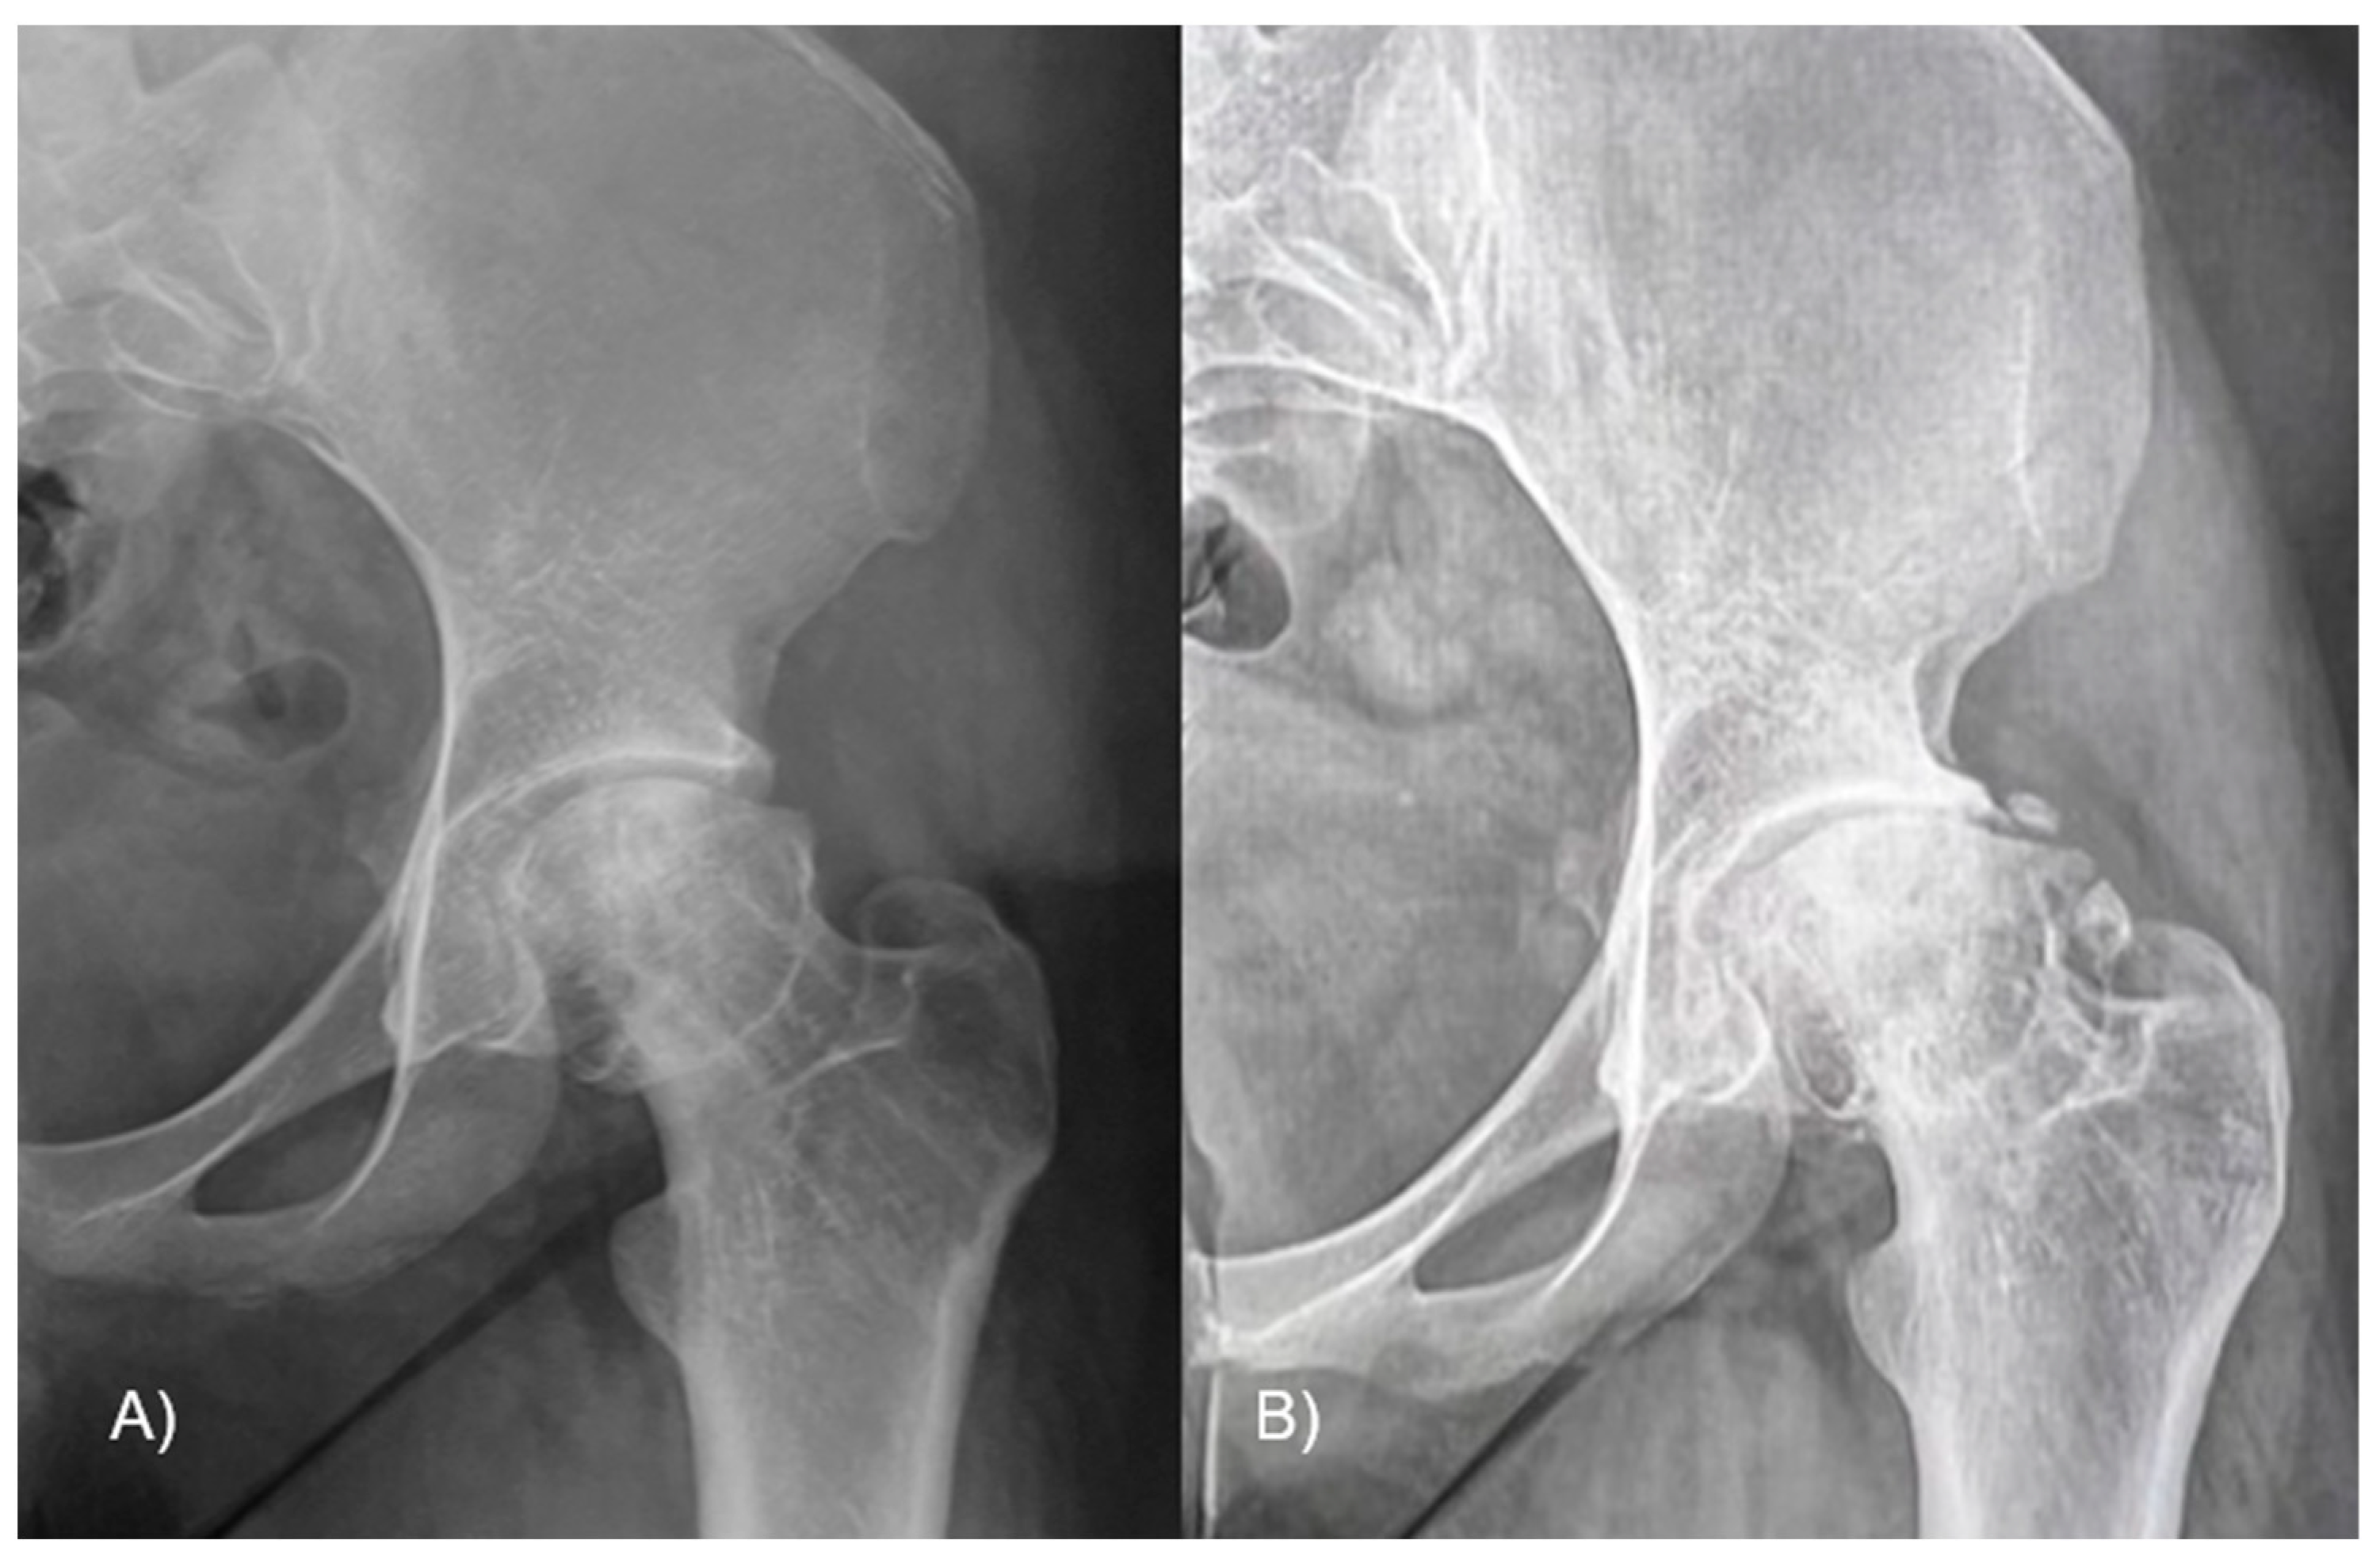

The epiphyseal–metaphyseal offset was assessed in the frog-leg lateral view by determining the disparity between a line traced along the front border of the epiphysis, parallel to the femoral neck, and a line traced along the proximal–anterior edge of the metaphysis, also parallel to the femoral neck (Figure 5). A negative value means that the epiphysis lies posteriorly to the metaphysis. Finally, the presence of AVN or cartilage degeneration was evaluated at the latest available follow-up.

Figure 5.

The epiphyseal–metaphyseal offset was measured in the frog-leg lateral view as the difference between (E) a line drawn along the anterior edge of the epiphysis, parallel to the femoral neck, and (M) a line drawn along the proximal–anterior edge of the metaphysis, also parallel to the femoral neck. In figure (A) the offset is reduced due to the head slippage, while (B) after the reduction it is improved.